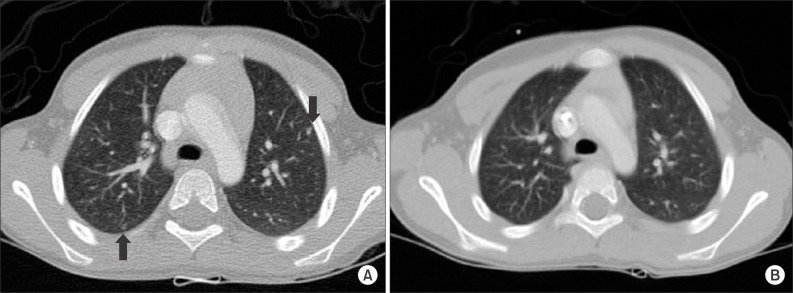

4 стадия – образуются метастазы спинного (головного) мозга, легких, печени, костей;

- рентгенография грудной клетки (выявляется смещение средостения, повышение уровня диафрагмы и присутствие метастаз в легких);